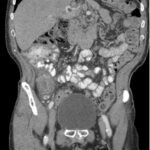

Small bowel diverticulitis is an uncommon subset of acute diverticulitis and can mimic many other intra-abdominal processes. As a result, imaging modalities such as ultrasound and computed tomography (CT) scan are especially important for timely recognition of diverticulitis and can expedite diagnosis and treatment and reduce complications. In the case described in this report, an 81-year-old male with history of esophageal cancer and recurrent diverticulitis with history of multiple bowel resections presented to the emergency department (ED) with right lower quadrant abdominal pain and constipation. Findings on ultrasound were suggestive of diverticulitis, and findings on CT of the abdomen and pelvis showed ileitis with phlegmon and micro-abscess suspicious for small bowel diverticulitis. ED providers should familiarize themselves with ultrasound findings of diverticulitis and be aware that diverticulitis can also present in the small bowel. Treatment of small bowel diverticulitis is similar to colonic diverticulitis.